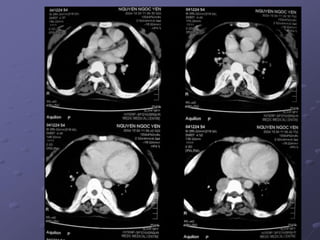

Case 1: Bệnh nhân nam 70 tuổi, vào viện với bệnh cảnh đau ngực nhiều ngày,

siêu âm dãn thất phải, tăng áp đm phổi. CT huyết khối động mạch phổi nhánh

chính 2 bên (mũi tên).

- Bệnh nhân được chuyển BVCR. Chẩn đoán tắc động mạch phổi 2 bên.

Case 2: bệnh nhân nam 61 tuổi, nhập viện vì đau ngực và khó thở.

- Siêu âm: dãn buồng tim phải, tăng áp động mạch phổi.

- CT huyết khối động mạch phổi phải và trái.

- Kích thước đm phổi gốc (d = 33 mm) lớn hơn động mạch chủ cùng lát

cắt…nghĩ tắc cấp.

- Điều trị tiêu sợi huyết tại BVTMAG. Đáp ứng tốt.